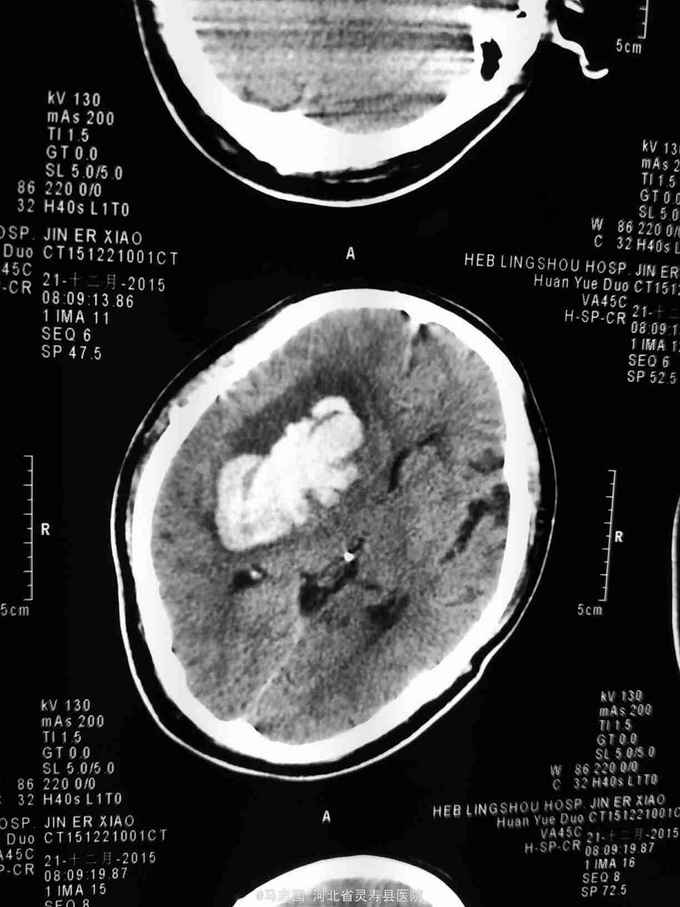

突发意识不清2小时入院,既往高血压病史,未规律服药。患者缘于2小时前劳动时,突发左侧肢体无力,烦躁不安,随即昏迷,无恶心呕吐,无肢体抽搐,无二便失禁,当地未予诊治,急打120接入院,急诊急查头CT:右侧基底节脑出血并脑疝形成,侧脑室内积血不除外,2.左额叶梗塞。为进一步诊治收住院。

呼吸20次/分,脉搏90次/分,血压210/90mmhg,中度昏迷,刺痛能定位,右侧瞳孔直径6mm,对光反射消失,四肢肌力不详,左侧肢体肌张力高,右侧肢体肌张力正常,左巴氏征阳性。

1.右侧基底节脑出血并脑疝形成2.高血压3级 极高危。急诊行血肿清除,去骨瓣减压术。术后给予降颅压,促醒保护脑神经等治疗。术后第二天复查CT如下